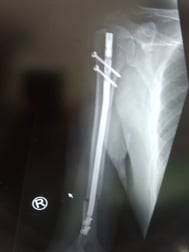

○上腕骨骨幹部骨折

二の腕を骨折してしまいました。救急で運ばれましたが、直ぐに処置はなく一週後に手術を受けました。骨にボルトを埋め込み固定する大手術です。

当患者さんは三週間が過ぎたころ、「痛みで夜まったく眠れない、痛み止めも全く効かない、

どうにかして下さい」と訴えて来られました。

見ると肘の周りが、かなりうっ血していて前腕の筋肉もコチコチになっていました。肩の関節の可動域もかなり制限されていました。当院ではまだ新鮮な術後だったので骨折部には触れず周りの皮膚を軽く軽擦(マッサージ)して、血腫には超音波治療をしました。するとみるみる痛みが軽減し夜も眠れるようになりました。整形外科の先生方は最新の治療で処置してくれますが患者さんの日常の苦しみにあまり耳を傾けてくれないようです。